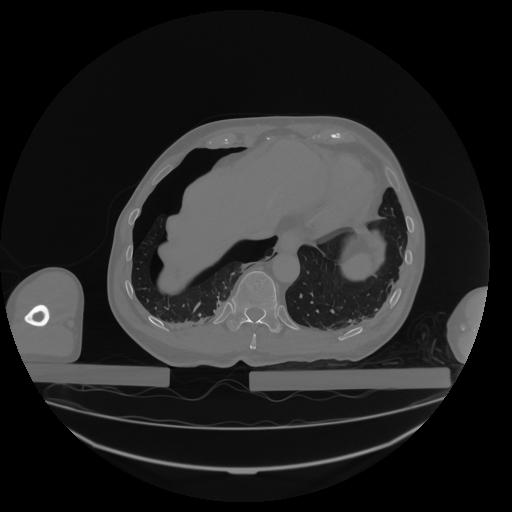

34 CUERPO,CE,Vol,1.0,CUERPO,,